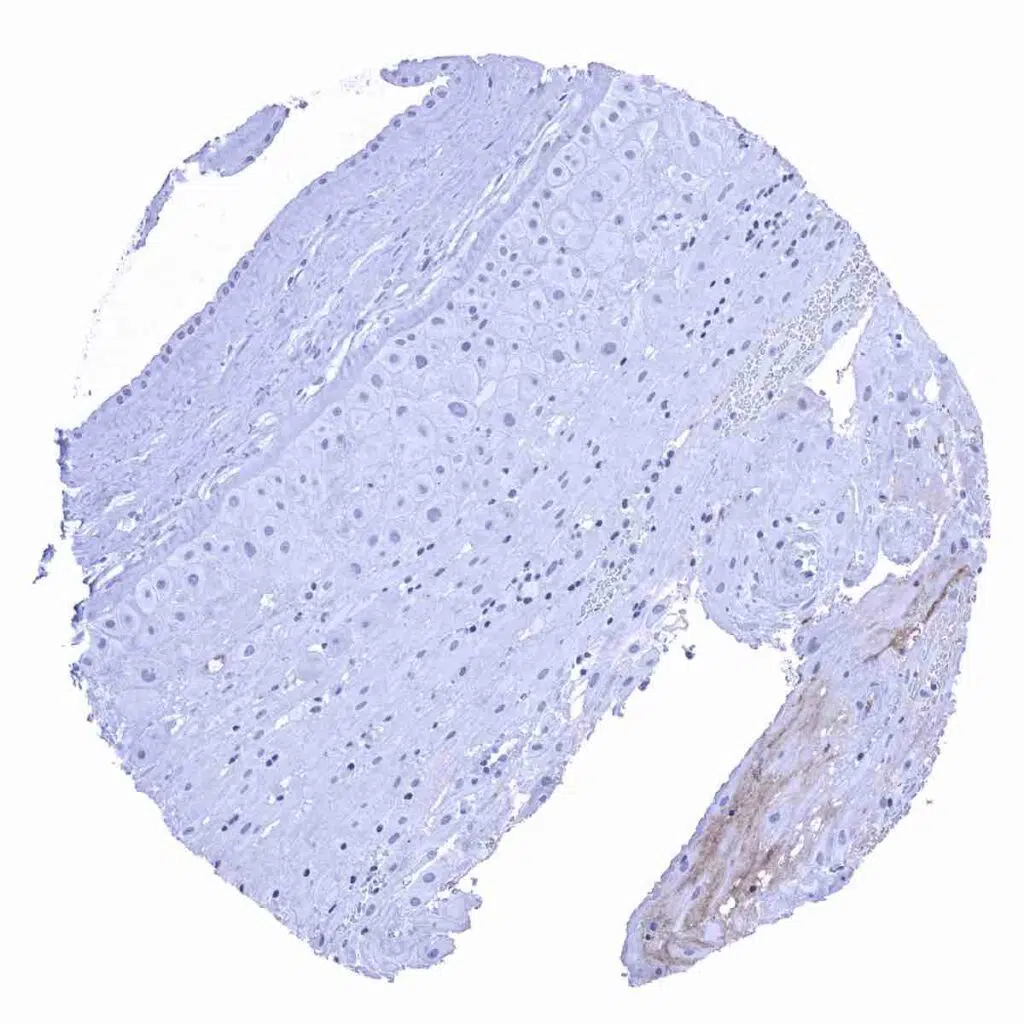

Esophagus, squamous epithelium – Few Rabbit anti-human IgA positive plasma cells are seen.